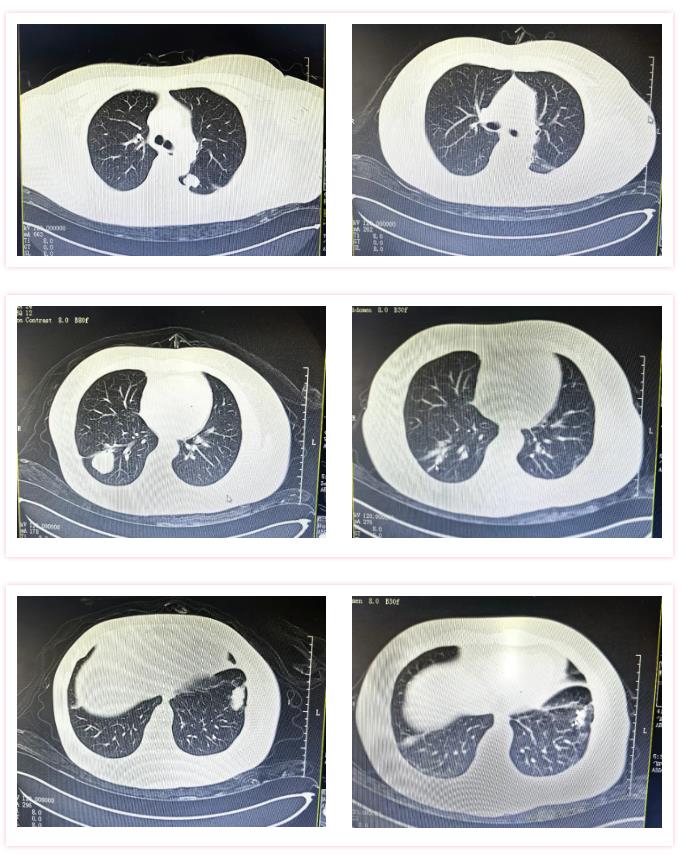

“双肺多发转移瘤,临近右下肺动脉、叶间胸膜、胸壁胸膜粘连……”针对李姐的病情,医疗团队先后为她实施了2次肺转移瘤冷冻消融术,并同步穿刺活检,活检结果再次证实为:原宫颈癌转移。

△三次碘粒子植入前(左图)后(右图)对比